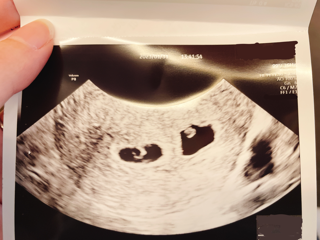

写真:5w3d:mamyyyさん

生理が遅れて3日でドゥーテスト陽性、最終生理からの計算で5週3日の今日、初受診で胎嚢と赤ちゃん、心拍まで確認できました!

赤ちゃんは4.5ミリだと言われました!待望の2人目、どうか無事成長してくれますように...